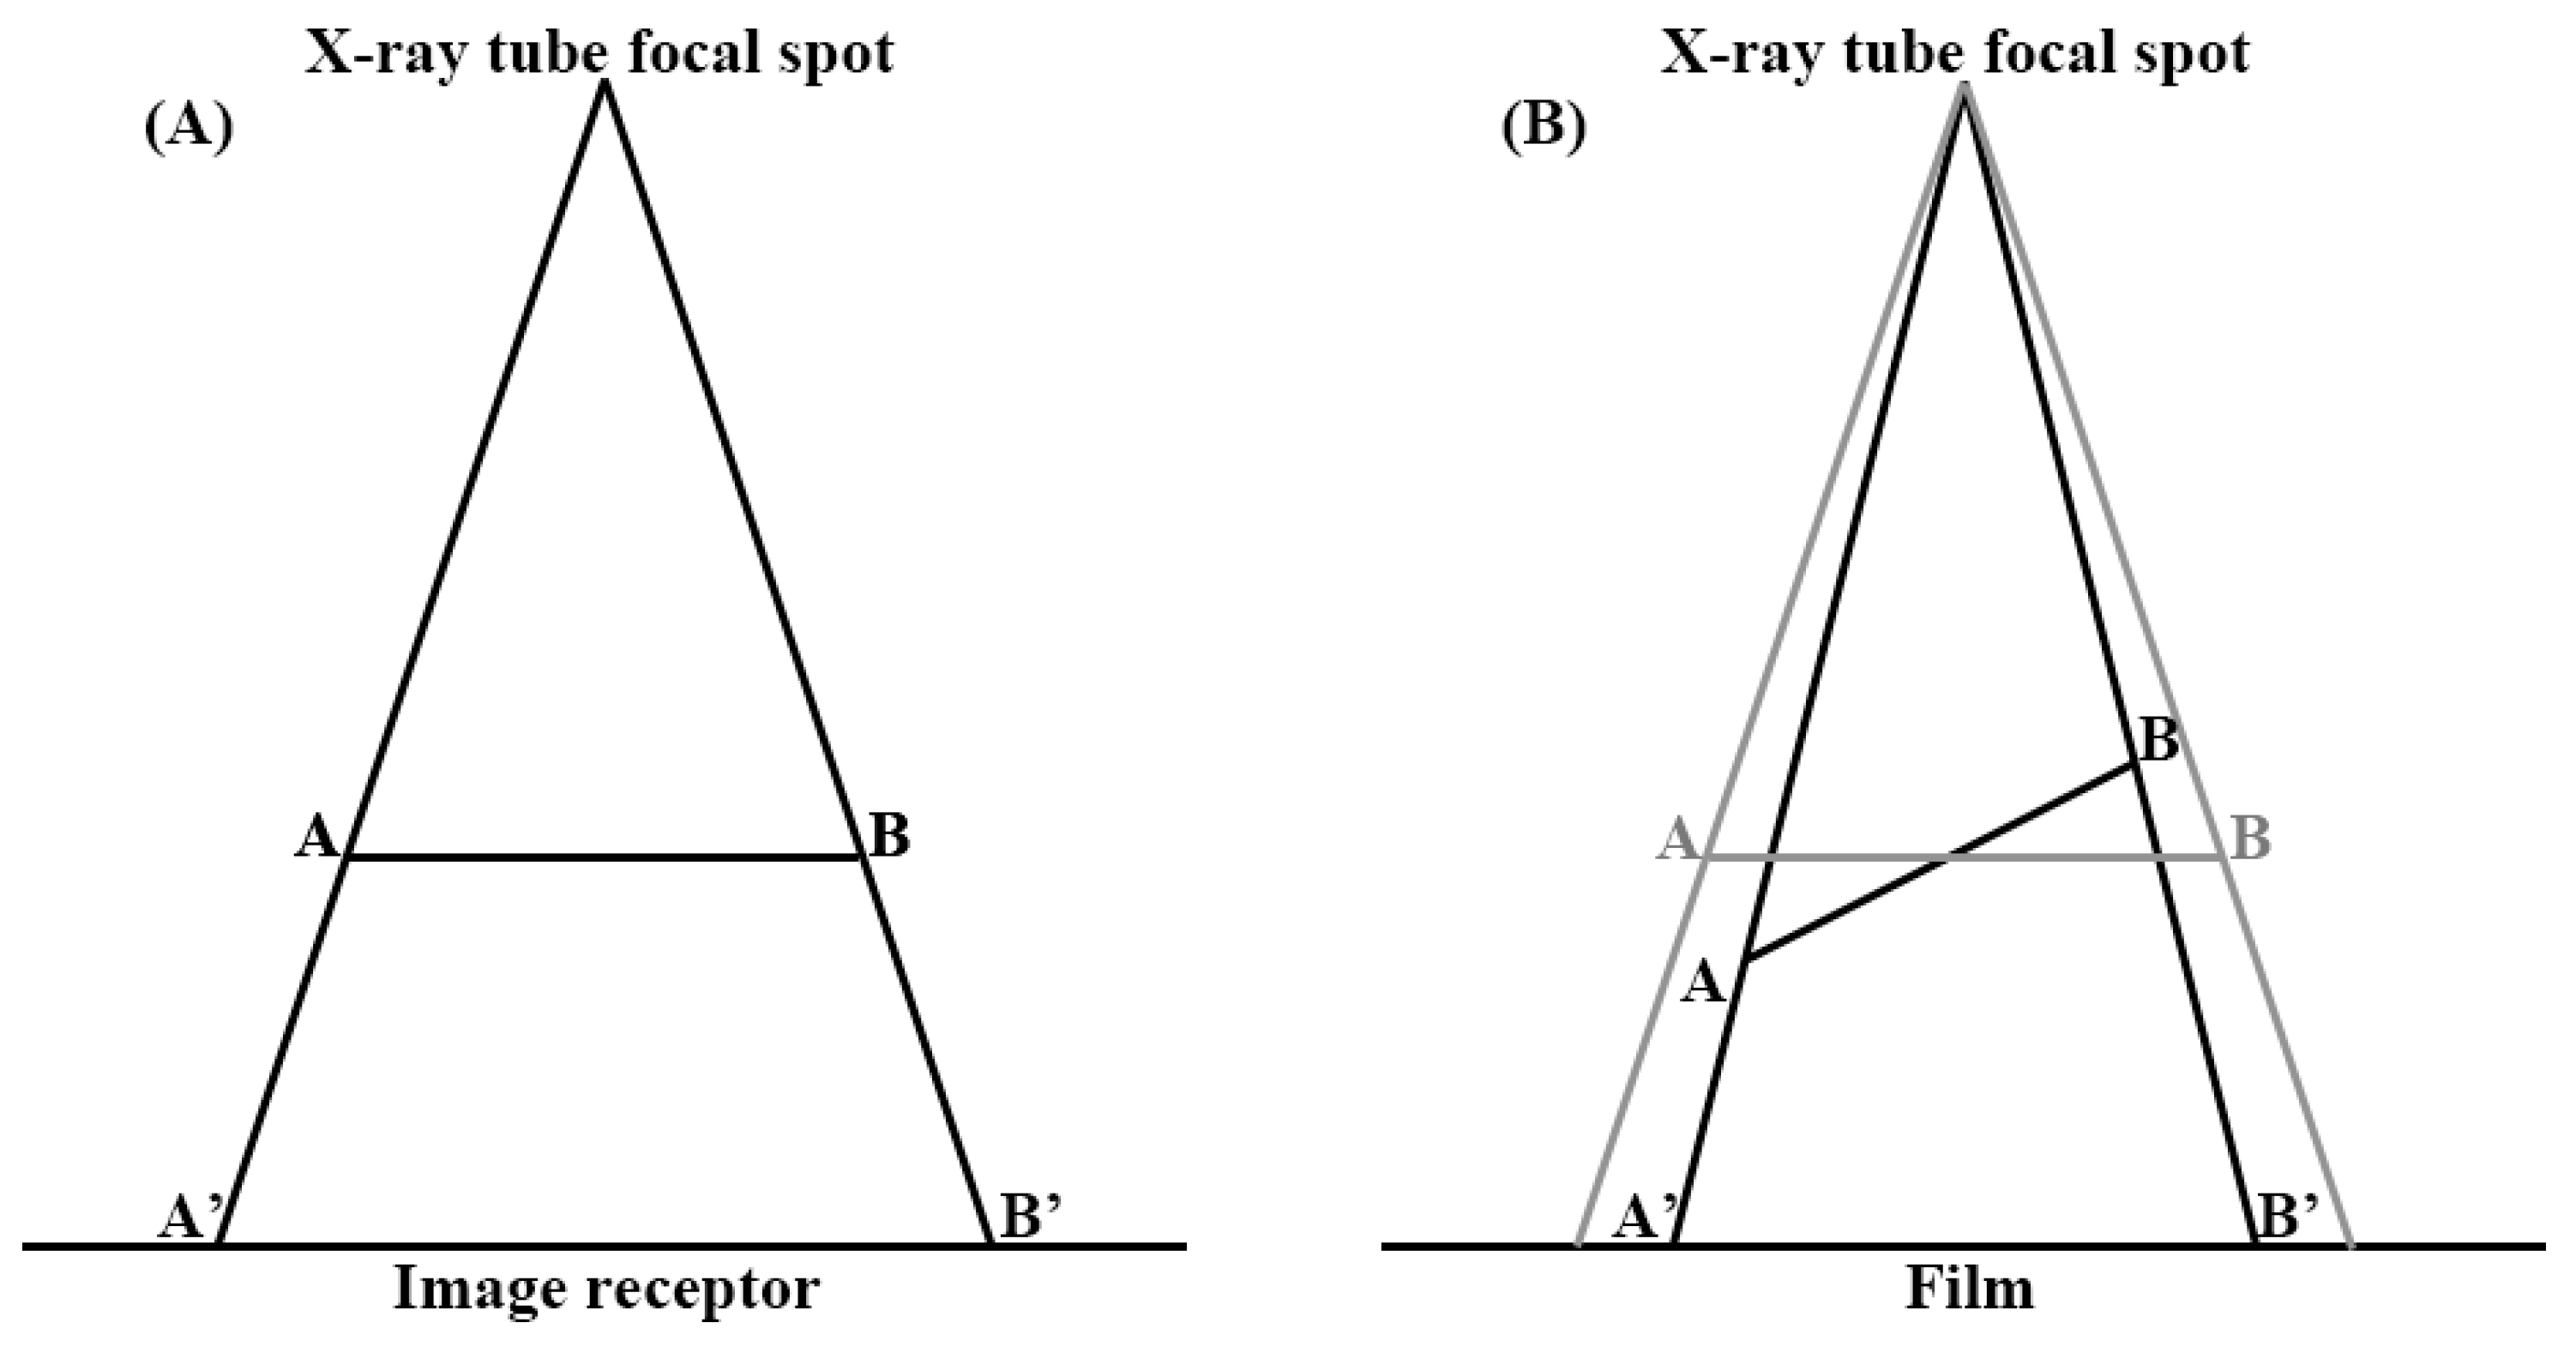

2.2. Radiologic Parameters